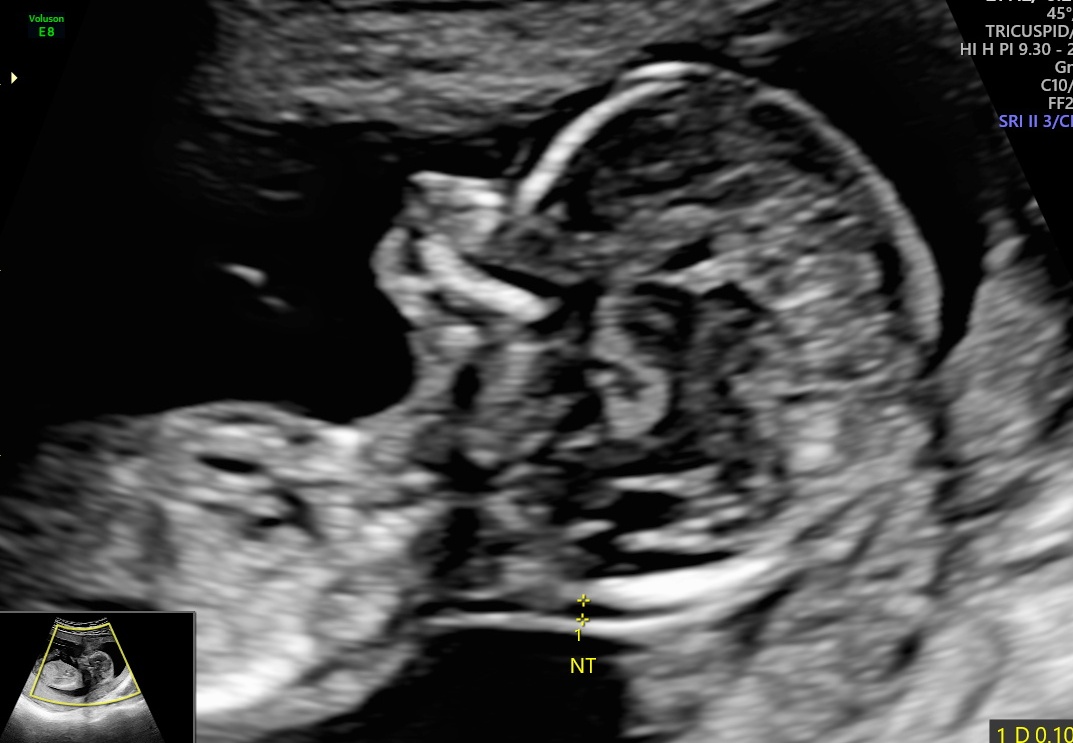

From www.fetalultrasound.com

Complex Nuchal Mass Turners Syndrome On Ultrasound Certain features on an ultrasound image may raise suspicion that your baby has turner syndrome or another genetic condition. Turner syndrome (ts) was first described by henry turner in 1938 and was then known to be secondary to karyotypic variation. Lymphoedema, a condition that causes swelling in the body's tissues, can affect unborn babies with turner syndrome, and may be. Turners Syndrome On Ultrasound.